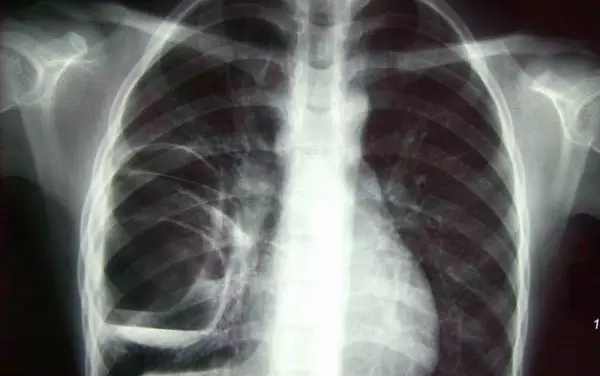

X光攝影(平片)

X光會(huì)穿透人體,由于人體各部位組織密度厚度不同,吸收的X光機(jī)的劑量不同,到達(dá)底片的X光的量不同,底片就會(huì)顯現(xiàn)出黑白不同的顏色。

優(yōu)點(diǎn):快捷、價(jià)廉、影像清晰度高

缺點(diǎn):平片檢查,無法進(jìn)行三維檢查

3、胸部——粗看X光平片,細(xì)看CT

X光胸片可粗略檢查肺、心影、主動(dòng)脈弓、肋骨等,可以檢查有無肺紋理增多、肺內(nèi)較大腫塊、主動(dòng)脈結(jié)鈣化等。胸部CT檢查顯示出的結(jié)構(gòu)更清晰,對胸部病變檢出敏感性和準(zhǔn)確性均優(yōu)于常規(guī)X光胸片,特別是對于篩查早期肺癌有重大意義。而磁共振成像對于肺內(nèi)疾病的診斷,應(yīng)用非常有限。